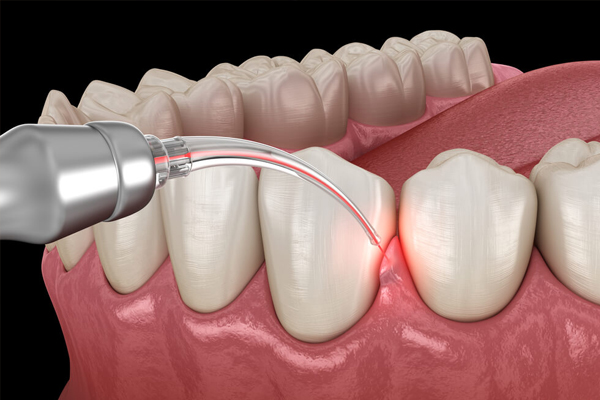

Laser dental treatment uses advanced cautery machines for precise care on both hard and soft tissue lesions. It minimizes discomfort, speeds up healing, and reduces infection risks. This technology also enables non-invasive biopsies of precancerous lesions, enhancing early detection with faster recovery. Laser treatments improve patient comfort by requiring less anesthesia and shortening recovery time.